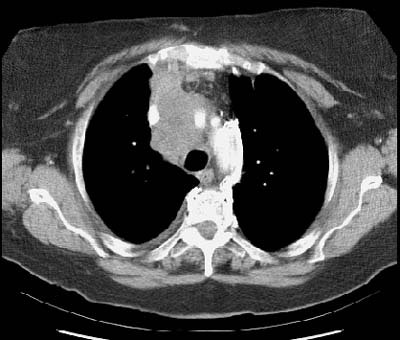

Example 1: False-positive exam -- this patient had a right upper lobe squamous-cell carcinoma. The mass is adjacent to the superior vena cava. Abnormal mediastinal N2 (yellow arrow) nodes were identified by the staging CT exam. Contralateral N3 nodes (white arrows) were borderline abnormal by size criteria. The patient underwent medianstinoscopy and anterior mediastinotomy (Chamberlain procedure) for pre-operative staging -- both of which were negative for malignant cells. The patient had underlying interstitial lung disease which has been associated with the presence of reactive mediastinal adenopathy. At surgery the patient was found to have ipsilateral hilar adenopathy (N1) and parietal pleural invasion (T3 tumor) or a stage IIIA.